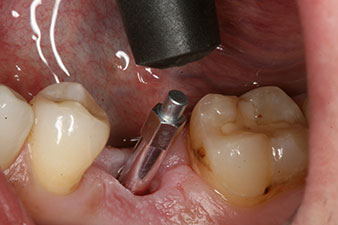

Nach Abheilung der Weichgewebe wurde vor der weiteren prothetischen Versorgung die Implantatstabilität erneut bestimmt.

Beide Werte waren praktisch unverändert und lagen im Übergang vom mittleren in den hohen Bereich – wobei der niedrigere Wert immer als therapiebestimmende Referenz dient.

Damit konnten eine erfolgreiche Osseointegration und ausreichende biologische Stabilität dokumentiert werden, die eine Abformung in derselben Sitzung erlaubte.

Die Implantatstabilität wird besser als Mikromobilität beschrieben und am sichersten mit der Resonanz-Frequenz-Analyse (RFA) bestimmt (7, 8). Die Messungen erfolgen, wie im Fallbeispiel, am besten in zwei Richtungen (9). Die entsprechende Technik ist im Implantologiemotor Implantmed optional als andockbares Modul verfügbar. Ein separates Gerät ist also nicht erforderlich. Für die Therapie zählt immer der jeweils niedrigere Wert. Messwerte werden als Implantat-Stabilitäts-Quotient (ISQ) am Touchscreen des Implantologiemotors angezeigt. Sie lassen sich, ebenso wie die Drehmomentkurve beim Einbringen und Daten zur Implantatbettaufbereitung, auf einem USB-Stick aufzeichnen und für die patienten- und implantatbezogene Dokumentation nutzen. Insgesamt handelt es sich – ganz besonders in Verbindung mit dem Implantmed von W&H – um eine sehr anwenderfreundliche und zuverlässige Technik für den implantologischen Alltag.